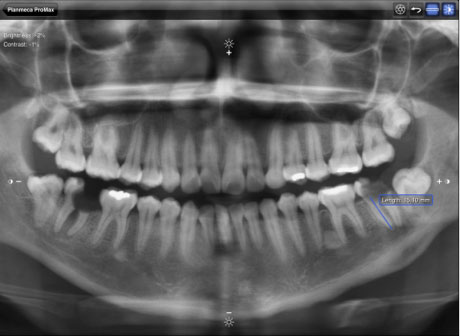

OPG panoramatická snímka – 12 €